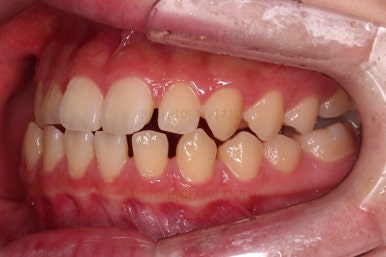

동래교정치과 초진 시 입안의 모습입니다.

치아가 벌어진 것도 벌어진 것이지만 교합이 전혀 안되고 있었어요.

틈새도 아랫니에 훨씬 많았고요.

윗니가 있는 위턱뼈가 전반적으로 아래턱에 비해 3차원으로 작은 양상이었습니다.

이번 환자분은 아랫니가 전반적으로 앞이든, 뒤든, 양옆으로든 넓어져 있는 양상이었고 그래서 아랫니에 틈도 많고 아래 앞니도 밀려나와 있는 양상인거죠.